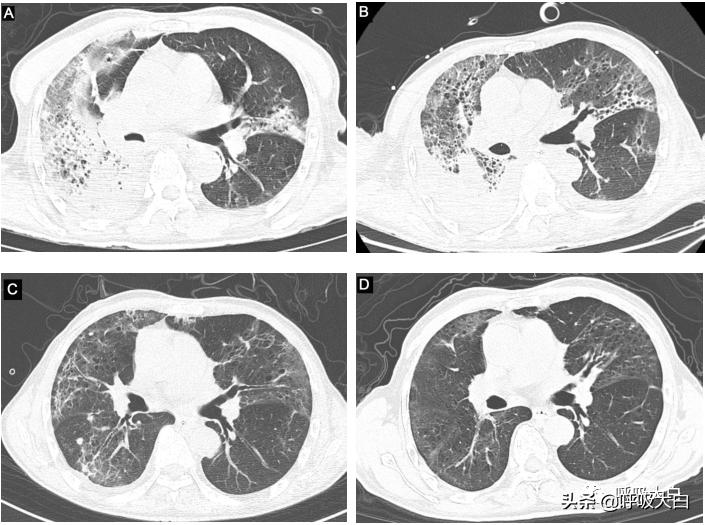

病例1 男,68岁,因“发热5d,咳嗽咳痰2d”入院。患者入院前5d出现高热,最高体温40.3℃,2d前出现咳嗽咳黄痰,在当地住院予头孢曲松抗感染等治疗,症状无好转,转来我院就诊。入院查体:T39.6℃,R32次/min,BP152/59mmHg,HR110次/min,鼻导管5L/min吸氧时氧饱和度96%;左肺呼吸音粗,右肺呼吸音较低,右肺可闻及湿啰音。胸部CT:右肺为主炎症伴实变、间质炎;血常规:WBC6.4x10^9/L,N 96.1%;hs-CRP:400mg/L;血气分析:PH值7.53,氧分压53mmHg,二氧化碳分压28mmHg,氧合指数200mmHg;PCT:9.34ng/ml。

入院后予以哌拉西林他唑巴坦针4.5g q8h联合莫西沙星针0.4g qd,抗感染,无创呼吸机辅助通气。初始治疗后病情无明显改善,仍持续高热且呼吸窘迫,改气管插管下呼吸机辅助通气,床边行支气管镜检查,取肺泡灌洗液送检NGS。2日后NGS报告提示病原体为鹦鹉热衣原体,诊断重症肺炎(鹦鹉热衣原体感染),加用多西环素胶囊0.1g,q12h抗感染。对患者常规病原体检测均阴性。5日后体温正常,症状及复查胸部CT均好转。患者入院及复查见图1:A入院时,BC治疗期间,D出院时。

图1